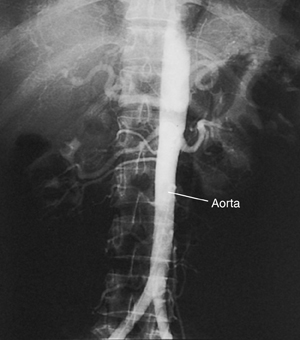

Aortic Angiogram

An aortic angiogram is a test that takes pictures of the aorta. This is the main blood vessel that carries blood from your heart to the rest of your body. The test can show problems with your aorta. These include a blockage or an aneurysm (a balloon-like bulge in the wall of the aorta).

Angiogram of normal aorta.